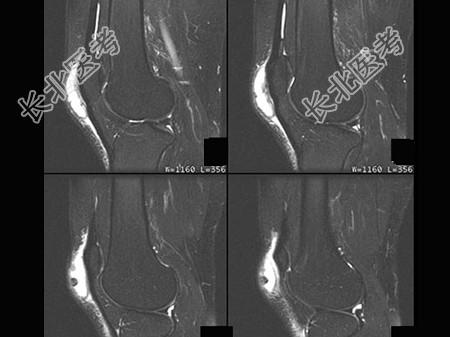

- 单项选择题男,20岁, 膝关节前方肿痛,轻度发红、发热, 结合图像,最可能的诊断是 ( )

E、髌前囊炎